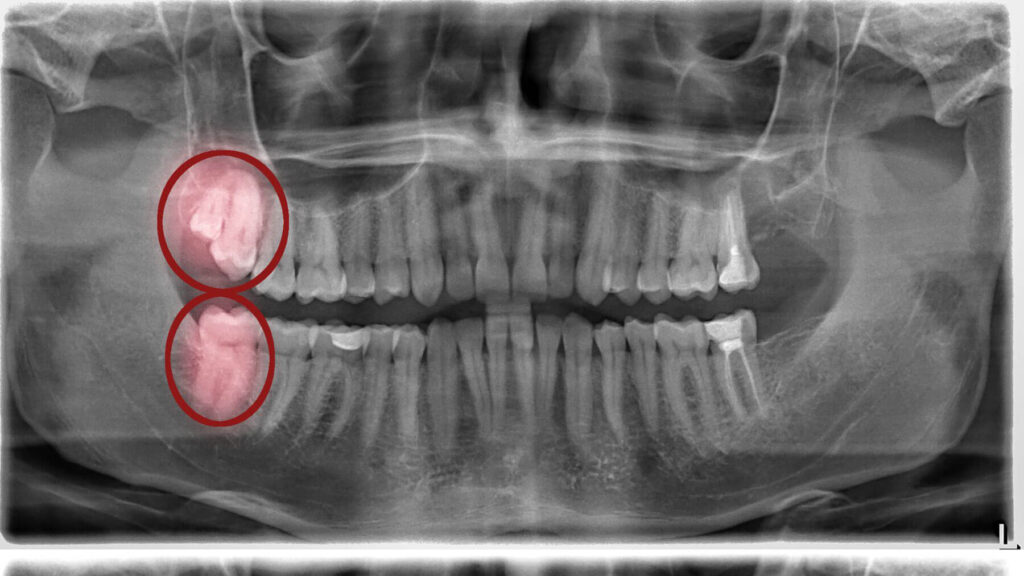

The wisdom teeth eruption timeline can vary, but generally follows a pattern. As mentioned, the 17-25 age bracket is typical. During this time, your jaw has usually reached its adult size, which ideally provides enough space for these last molars to emerge without issues. The process isn’t usually sudden; it’s a gradual unfolding. You might feel a tooth partially erupt, then stop for a while, and then continue its journey weeks or even months later. This on-again, off-again pattern is completely normal. Dental development involves a complex sequence, and wisdom teeth are the final act. Sometimes, due to lack of space, these teeth might only partially emerge, leading to what’s known as an impaction. Our approach at Smiles for Health DDS focuses on anticipating these developments. By utilizing diagnostic tools, we can get a clear picture of how your wisdom teeth are developing. If there’s a risk of impaction or other complications, we’ll discuss options like dental extractions to prevent future problems. We believe in being proactive, ensuring your long-term oral health.

Unfortunately, no, not all wisdom teeth erupt completely, and this is where potential problems can arise. Often, there isn’t enough space in the jaw for these final molars to emerge fully and properly align with your other teeth. When a wisdom tooth only partially breaks through the gum line, it’s known as a partial eruption. This can create a small flap of gum tissue over the tooth, which is a perfect breeding ground for bacteria and can lead to infections, pain, and swelling. Even more commonly, wisdom teeth can become impacted, meaning they are trapped beneath the gum line or bone, unable to erupt at all or growing in at an awkward angle. This impaction can lead to a range of issues, from chronic pain and damage to neighboring teeth to the development of cysts or tumors. Knowing when to see a dentist is crucial if you suspect a partial eruption or impaction. If you experience persistent discomfort, swelling, or difficulty opening your mouth, it’s important to schedule an appointment. Our team at Smiles for Health DDS can assess the situation with X-rays and recommend the best course of action, which might include dental extractions to prevent further complications and protect your overall wellness dentistry. Don’t let impacted wisdom teeth disrupt your life – secure your slot for a consultation with Smiles for Health DDS now before discomfort escalates! Visit our contact us or call us directly.